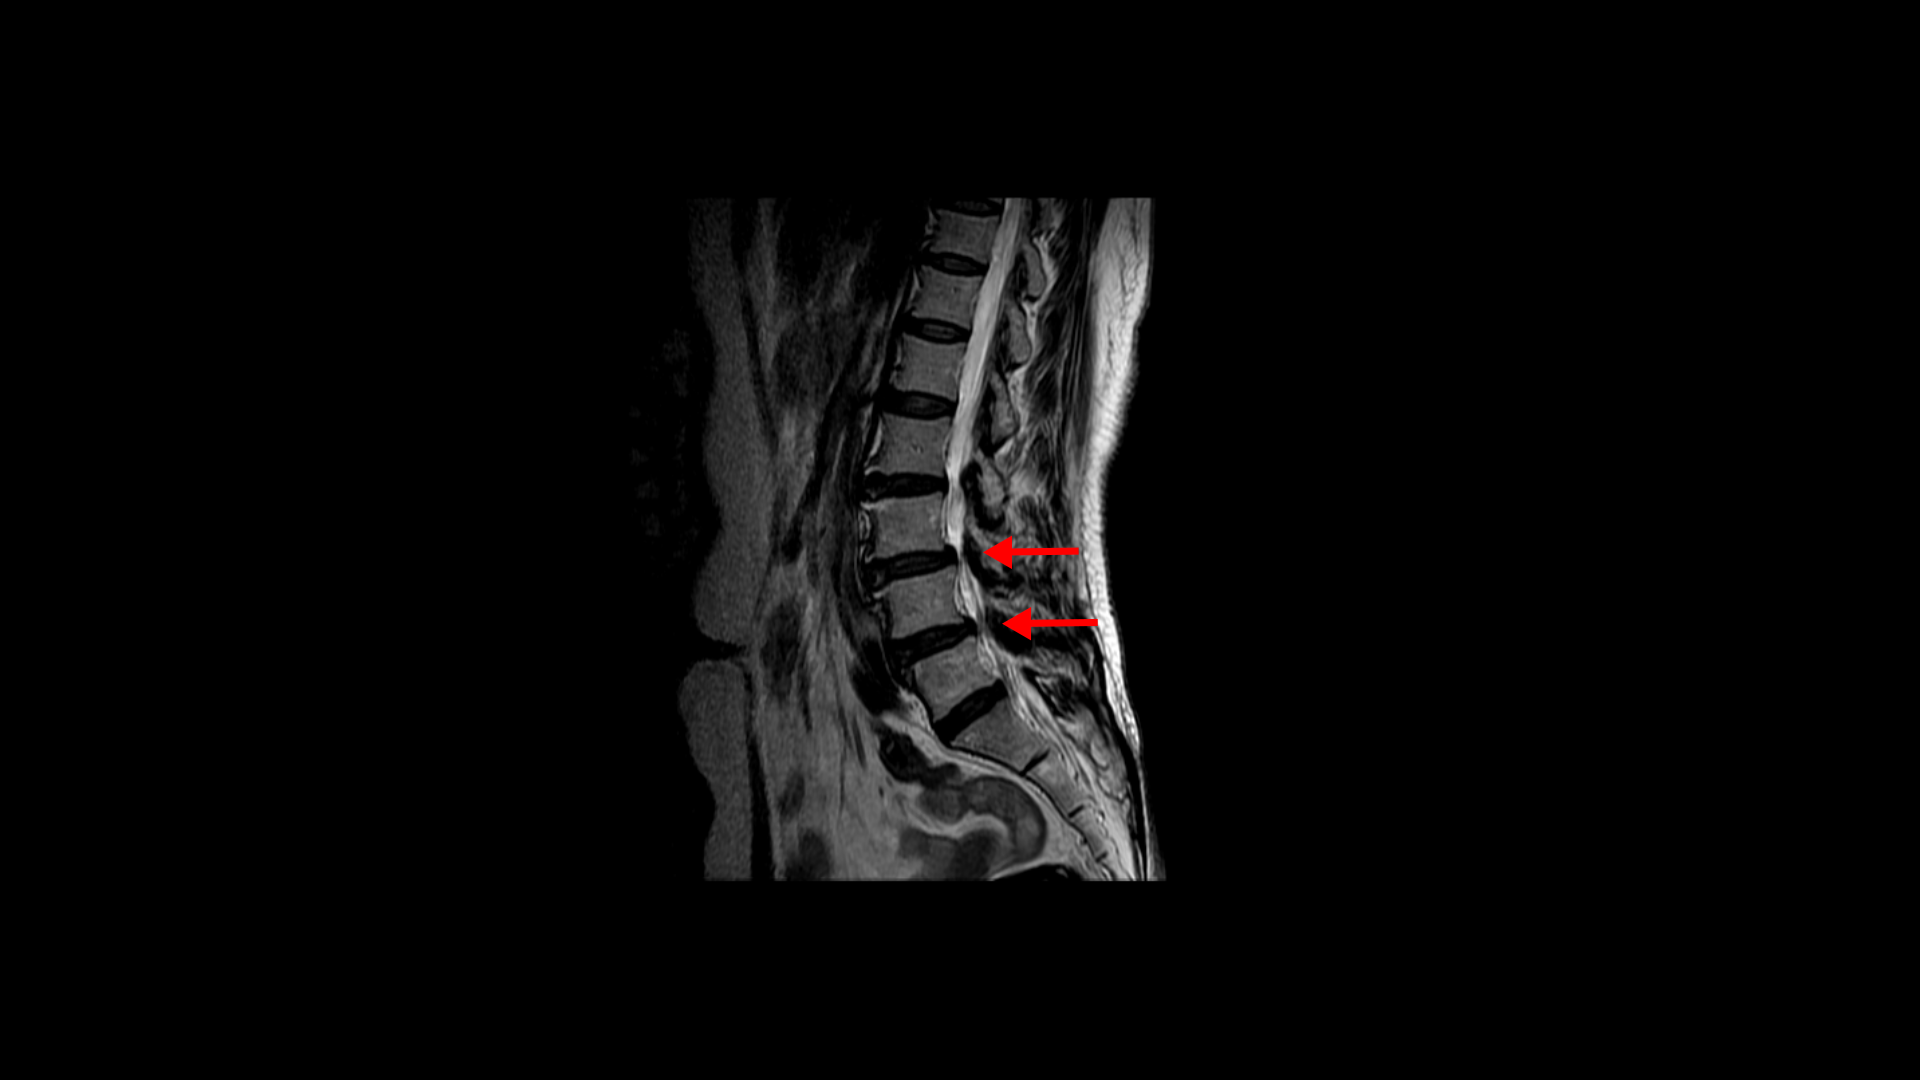

우선 이 환자분의 MRI를 함께 보겠습니다. 이 환자분의 척추에는 3번 4번과 4번 5번에 각각 1단계의 전방전위증이 있습니다.

3번 4번에는 왼쪽으로 디스크 탈출이 있고

중심성 협착도 있습니다.

그리고 4번 5번에도 왼쪽으로 퇴행성디스크와 후관절의 퇴행으로 신경 가지가 나가는 구멍이 좁아져 있습니다.

그리고 중심성 협착도 있습니다.

그런데 이 환자분의 제일 불편한 증상은 왼쪽이 아니고 오른쪽 엉치와 다리 증상입니다. 이분 오른쪽 신경 구멍들을 보면 전부 다 넓게 잘 열려 있습니다.

엉치와 다리 방사통을 일으킬만한 특별한 신경 눌림이 보이지 않는 것입니다. 그럼에도 불구하고 여러 마디의 전방전위증과 척추관 협착 그리고 디스크 탈출이 있으니까 그것을 원인으로 보고 신경 주사도 맞고 시술도 받으셨습니다. 그러나 별 효과는 없었습니다. 그리고 대학병원에서도 결국은 수술밖에 방법이 없다고 수술을 권유하였습니다.